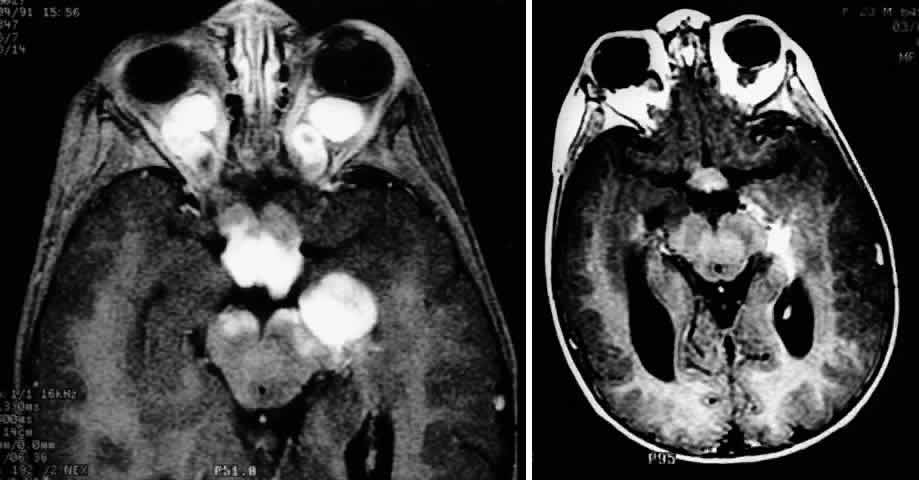

MRI has replaced CT scanning as the optimum test for imaging optic gliomas (Fig. 4 A and B). Optic gliomas have normal to slightly prolonged T1 relaxation times and appear isointense to slightly hypointense to normal brain on T1. Because many of these tumors have prolonged T2 relaxation times, images that are T2 weighted may be used to assess gross tumor margins and posterior extension.72 Optic nerve gliomas often demonstrate minimal enhancement after administration of contrast. To improve MR imaging of optic nerve lesions, a gadopentetate dimeglumine enhancement technique combined with fat suppression can be utilized. Unlike meningiomas, the thickened sheath from arachnoid hyperplasia associated with gliomas will not enhance.77 Although imaging should initially be performed in the axial plane to allow visualization of both the optic nerve and the posterior optic pathways, sagittal views are helpful in demonstrating chiasmal involvement; coronal views can be utilized to delineate intracanalicular tumor.78

Fig. 4. A. T1-weighted sagittal MRI of a patient with neurofibromatosis type 1, demonstrating enlarged optic chiasm consistent with optic glioma. B. T1-weighted coronal image with gadolinium and fat suppression in the same patient, demonstrating the chiasmal glioma.

Fig. 2. Contrast-enhanced T1-weighted axial MRI of the orbits of the patient in Figure 1, demonstrating a large optic pathway glioma with posterior extension into the optic tracts and radiations. (Courtesy of Orlando Ortiz, MD, and Jeffrey Hogg, MD)